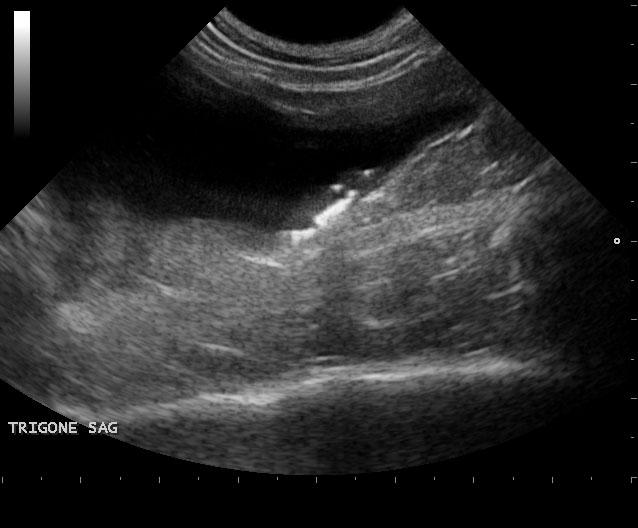

The left kidney was enlarged and measured 5.4 cm with pyelectasia and ill defined fat. Decreased corticomedullary definition was noted with focal capsular expansion at the caudal pole. The right kidney was also moderately to severely enlarged with corticomedullary and pelvic calculi. Loss of corticomedullary detail was noted. Minor subcapsular halo formation was noted with periserosal inflammation. The urinary bladder presented multiple small calculi measuring 0.1-0.3 cm. Mesenteric lymph nodes were enlarged and measured 1.5 cm and 1.8 cm. These lymph nodes were significantly hypoechoic, yet architecture was not distorted at this point. Hyperechoic reactive fat was noted.